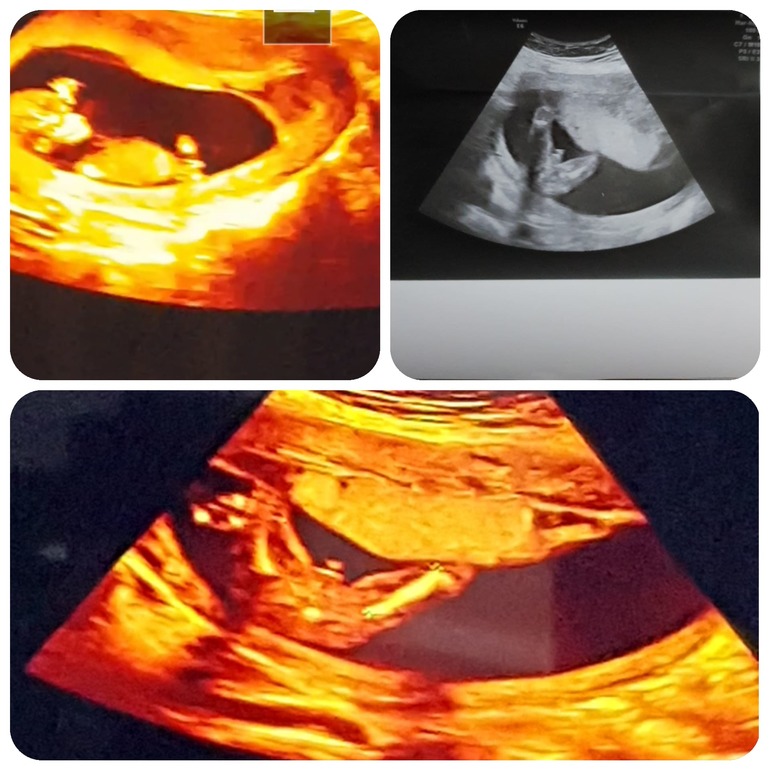

Это было УЗИ с дочкой